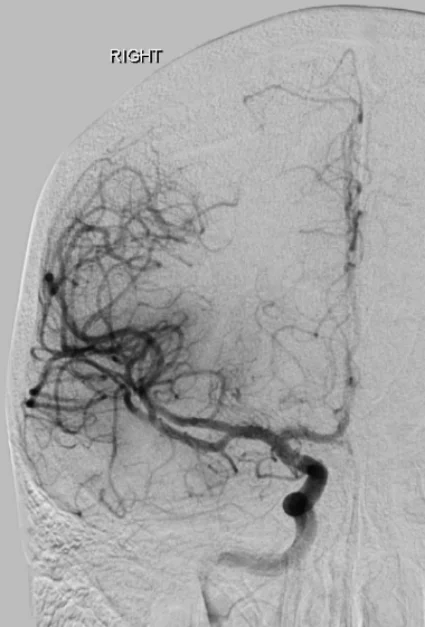

Lorsqu’une thrombectomie doit être réalisée, le patient est amené rapidement en salle d’angiographie et accueilli par l’équipe (paramédicaux, anesthésiste, neuroradiologue interventionnel(le)). En fonction de l’état de conscience, du confort et de la possibilité de rester immobile, la procédure est réalisée sous anesthésie locale ou générale. L’accès au réseau artériel se fait le plus souvent par l’artère fémorale au pli de la jambe ou l’artère radiale au poignet. Dans certaines situations, il est nécessaire d’accéder directement à l’artère carotide dans le cou. Une angiographie cérébrale est alors réalisée et permet de confirmer l’occlusion artérielle ou plus rarement de constater la recanalisation spontanée ou suite à la fibrinolyse intraveineuse. L’objectif est ensuite de naviguer un ou plusieurs cathéters au plus proche de l’occlusion voire au-delà afin d’essayer de retirer le caillot du corps soit en l’aspirant à travers un large cathéter, soit en le coinçant dans les mailles d’un stent qui est ensuite retiré du corps, soit par une combinaison des deux techniques. Plus rarement, en cas d’échec ou de constatation d’un rétrécissement structurel (sténose) de l’artère intracrânienne, à l’origine de l’occlusion, il est possible de dilater l’artère avec un petit ballonnet et éventuellement de laisser un stent en place. Lorsqu’un rétrécissement est constaté sur l’artère carotide dans le cou, il peut arriver que le même traitement (dilatation par ballonnet et mise en place d’un stent) soit nécessaire avant ou après la thrombectomie en elle-même, soit pour permettre le passage du matériel, soit pour éviter une récidive précoce. En fonction du type d’intervention, des médicaments antiagrégants peuvent être prescrits.